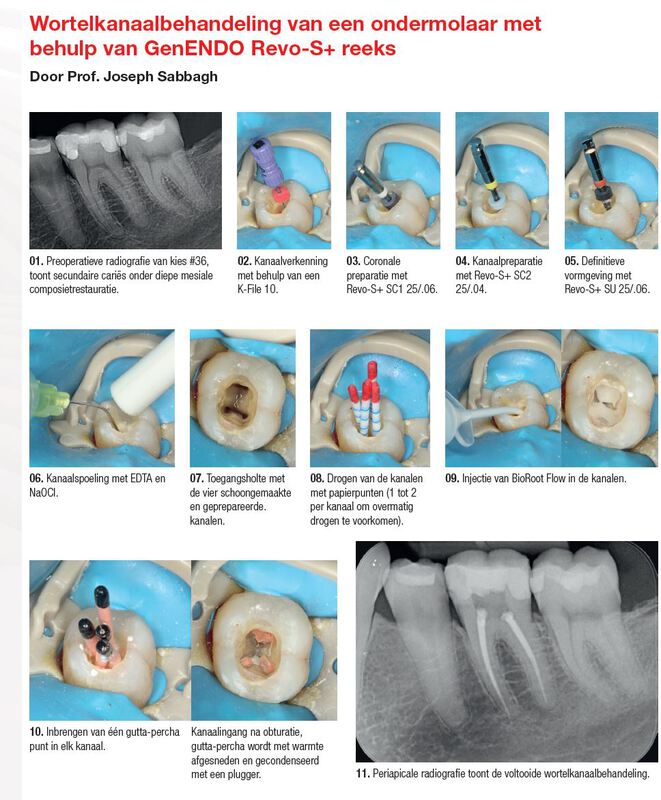

GenENDO Glider / 0,8 mm groefdiameter

16/.03

Beschikbaar in 3 lengtes (21, 25, 31 mm)

Steriel

Betrouwbare vijlen voor veilige resultaten:

Exclusief C.Wire warmtebehandeling voor:

- meer flexibiliteit

Vermindert onregelmatigheden

Betere breukbestendigheid

- Weerstand tegen cyclische vermoeidheid

Beperkte risico's op:

- Breuk*

- Vormafwijking kanaal**

- Schroefeffect**

* GenENDO Revo-S+, GenENDO Glider en GenENDO Remover

**GenENDO Revo-S+ en GenENDO Glider